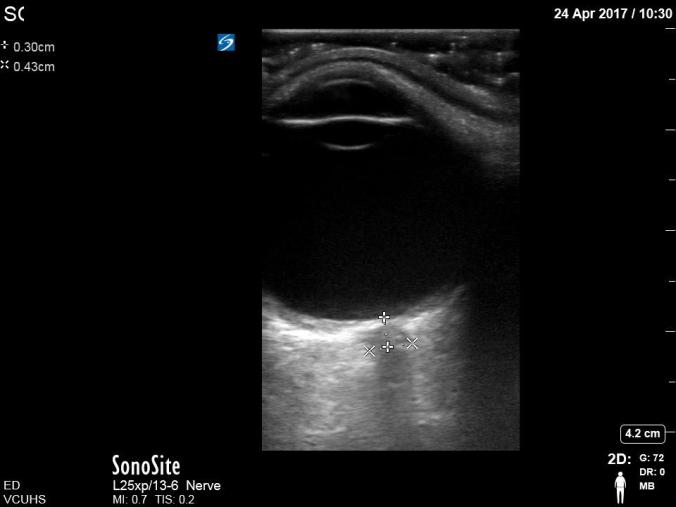

C. Measurement of optic sheath